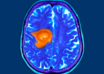

New discovery can help detect brain tumours